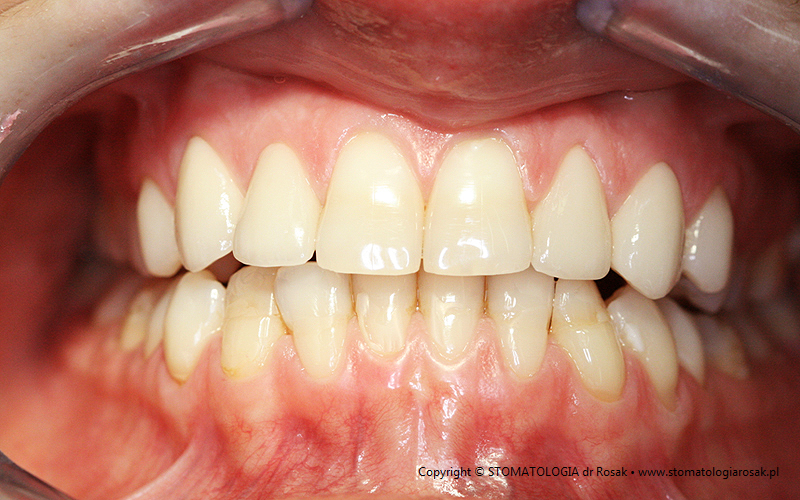

5. Pacjentka lat 18 z wrodzonym brakiem wielu zębów tzw. hipodoncją – rehabilitacja protetyczna z wykorzystaniem

stałych mostów porcelanowych na podbudowie metalowej.

| 5a. Stan przed leczeniem |